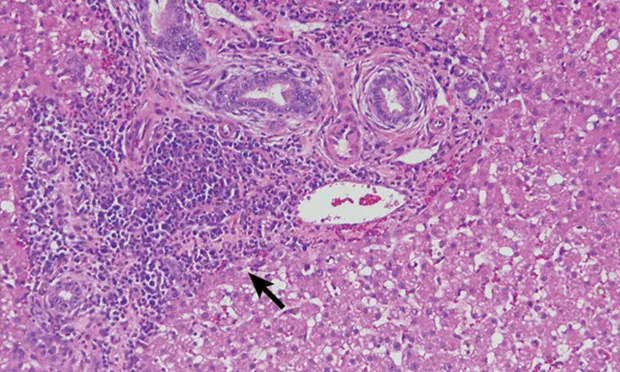

Figure 1

H&E-stained section (20× objective ) of a feline liver with periductal lymphocytic inflammation (arrow) centered around portal areas with concentric rings of fibrosis consistent with lymphocytic cholangitis.

The chronicity of lymphocytic cholangitis is believed to represent a later stage of neutrophilic cholangitis or may represent a separate disease entity. It is characterized by a moderate-to-marked infiltration of the portal areas by small lymphocytes with or without biliary hyperplasia, portal or periductal fibrosis, or bridging fibrosis (Figure 1). The underlying cause is unknown, but 1 possible cause is an immune disorder.<sup11 sup>